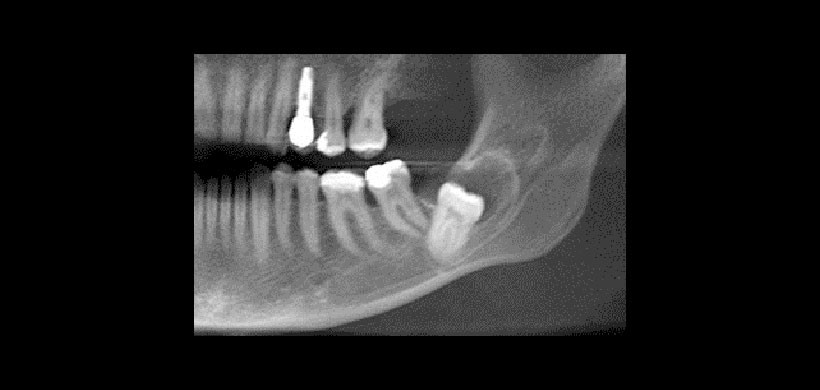

La única manera de reconocer los inicios de los procesos quísticos, sobre todo aquellos  asociados al folículo dentario como es el caso de quiste dentígero,  es sólo posible su visualización mediante los exámenes radiográficos, puesto que los quistes solo dan sintomatología cuando ya tienen un tamaño importante. Los estudios realizados en radiografías panorámicas demuestran que la radiolucidez del espacio peri coronario debe de tener un ancho de hasta 2.5 mm (medida desde el esmalte dentario hasta el la cortical del folículo dentario.

Fig 2.  El 24 % de todas las radiografías panorámicas en el que se muestra un espacio folicular mayor a 2.5 mm corresponden a patologías quísticas.

Fig 3. El quiste dentígero, en su variante folicular, es la patología más frecuentemente asociada al aumento del espacio folicular pericoronal de un diente impactado. Es muy complicado realizar su diagnóstico en su fase inicial ya que puede tratarse de una hiperplasia folicular. Por ende está indicada la exodoncia del tercer molar impactado.